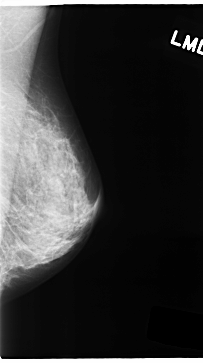

Digital Database for Screening Mammography

Volume: cancer_05 Case: C-0154-1

C_0154_1.LEFT_MLO

LEFT_MLO LINES 4712 PIXELS_PER_LINE 2632 BITS_PER_PIXEL 12 RESOLUTION 50 NON_OVERLAY